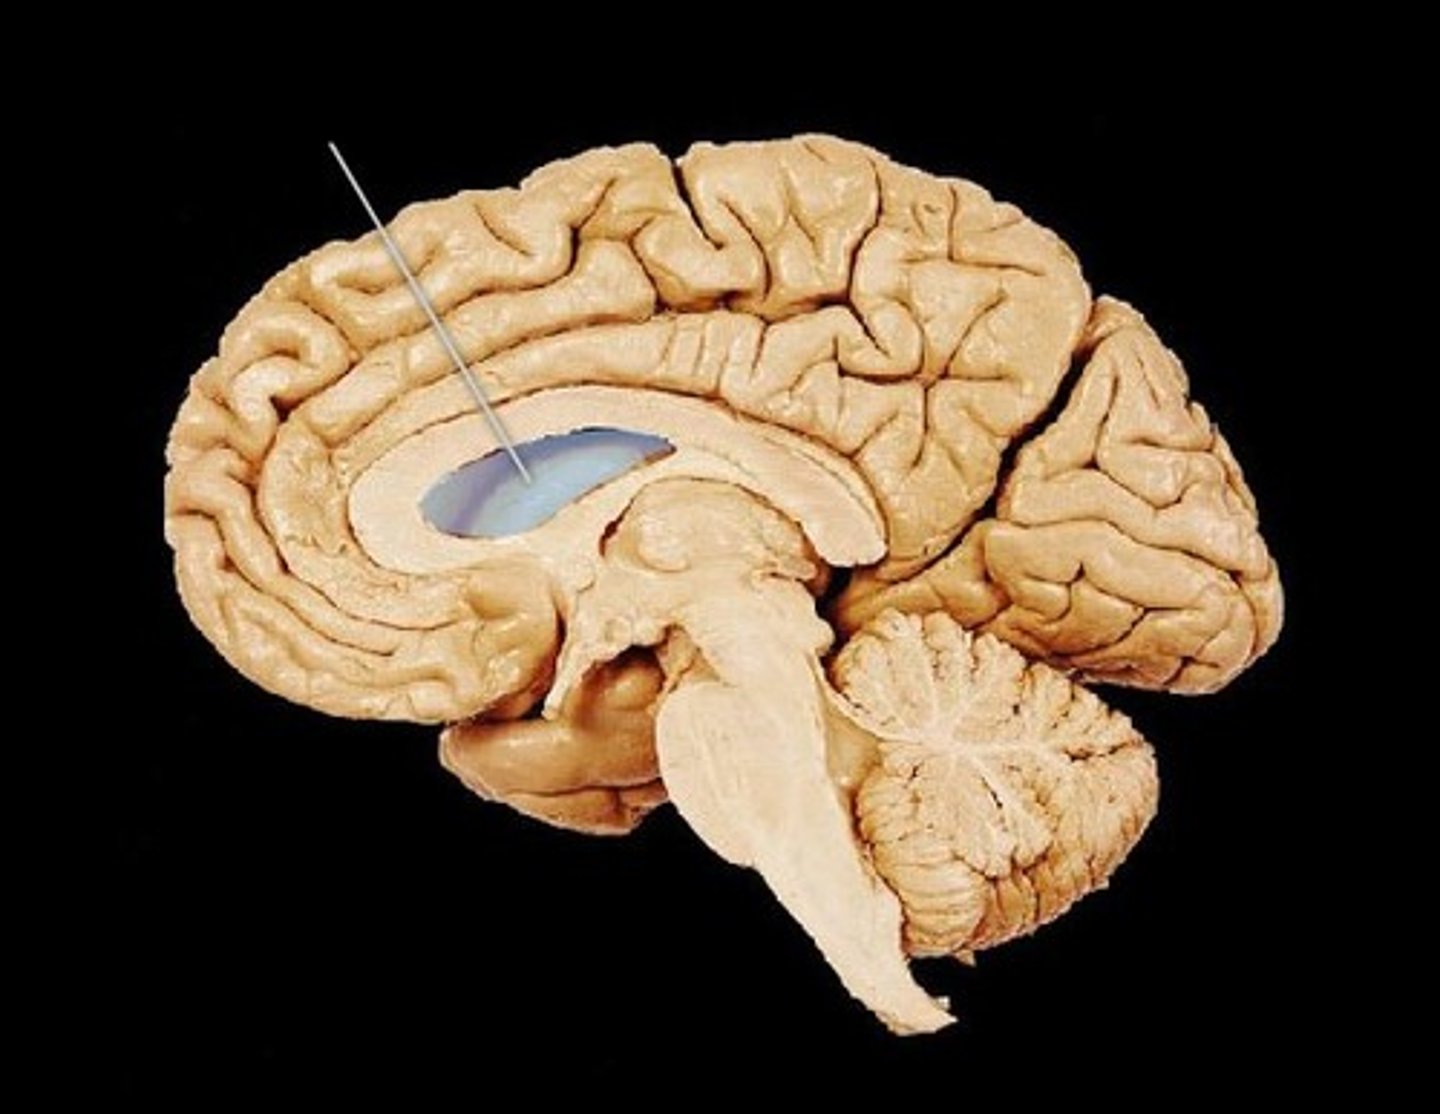

MIdsagittal View of brain

Lateral Ventricle

Third Ventricle

Cerebral Aqueduct

Forth Ventricle

Corpus Callosum

Fornix

Thalamus

Pineal Gland

Superior Colliculi

Inferior Colliculi

Midbrain

Hypothalamus

Cerebral Cortex Gray Matter (nerve cell bodies)

White Matter (myelinated nerve fibers)